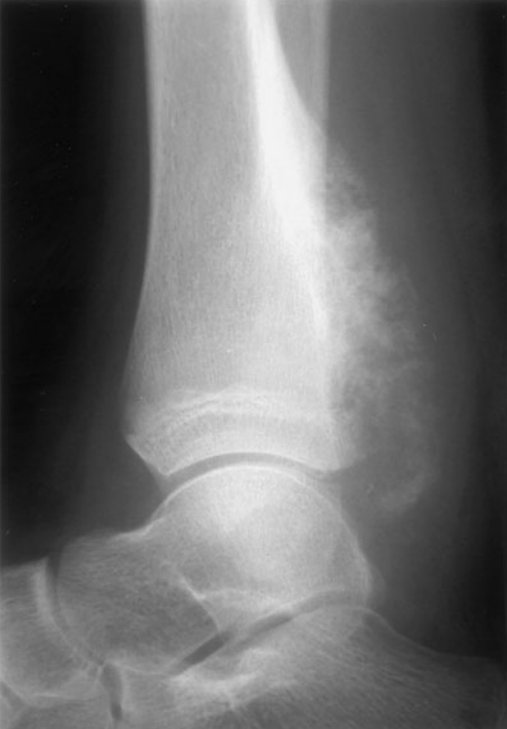

Osteosarcoma

Demographics: Occurs most commonly in the second decade of life, and a bit more commonly in boys than in girls. It occurs in all ethnic groups (in contrast, Ewing sarcoma, another bone malignancy, rarely occurs in blacks).

Symptoms: The lesion is found in the metaphyses of long bones, and usually presents with local pain and swelling.

Labs: Radiograph shows the expected “sunburst” pattern of bone formation.

Risks: Predisposing factors include a history of retinoblastoma, Li-Fraumeni syndrome, Paget disease, or radiotherapy. Any bone or joint “injury” not responding with conservative therapy within a short period of time should be evaluated.,

Over the previous 2 to 3 weeks, a very active 13-year-old white boy is noted by his family to have developed deep pains in his leg that awaken him from sleep. The family brings him to your office with a complaint of a swelling over his distal leg, which he attributes to his being kicked while playing soccer about 1 week ago. He has had no fever, headaches, weakness, bruising, or other symptoms. A radiograph of the leg is shown below. Which of the following is the most likely explanation for his pain?